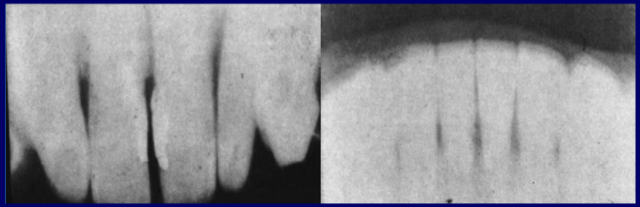

• Primera radiografía dental del mundo

Primera radiografía dental del mundo

Paciente y odontólogo: Dr. Otto Walkoff, Braunschweig, Alemania.

Tiempo de exposición: 25 minutos

Más tarde fue profesor de radiología, Munich, Alemania.